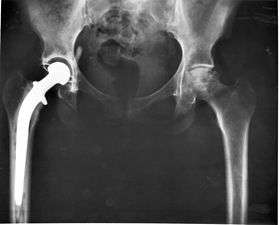

3. Class III devices generally require premarket approval (PMA) or premarket notification (510k), a scientific review to ensure the device's safety and effectiveness, in addition to the general controls of Class I. Examples include replacement heart valves, hip and knee joint implants, silicone gel-filled breast implants, implanted cerebellar stimulators, implantable pacemaker pulse generators and endosseous (intra-bone) implants.

Implants

An implant is a kind of medical device made to replace and act as a missing biological structure (as compared with a transplant, which indicates transplanted biomedical tissue). The surface of implants that contact the body might be made of a biomedical material such as titanium, silicone or apatite depending on what is the most functional. In some cases, implants contain electronics, e.g. artificial pacemakers and cochlear implants. Some implants are bioactive, such as subcutaneous drug delivery devices in the form of implantable pills or drug-eluting stents.

Implants, such as artificial hip joints, are generally extensively regulated due to the invasive nature of such devices.